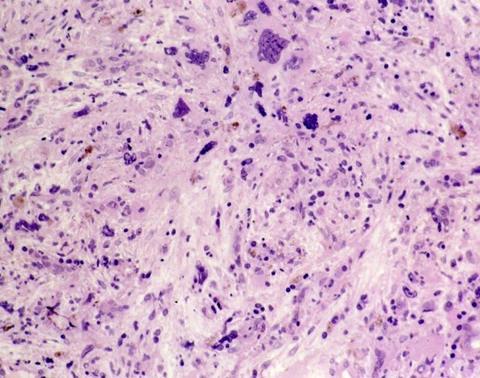

If approved, momelotinib will be the first treatment in the EU indicated for myelofibrosis patients with moderate to severe anaemia.